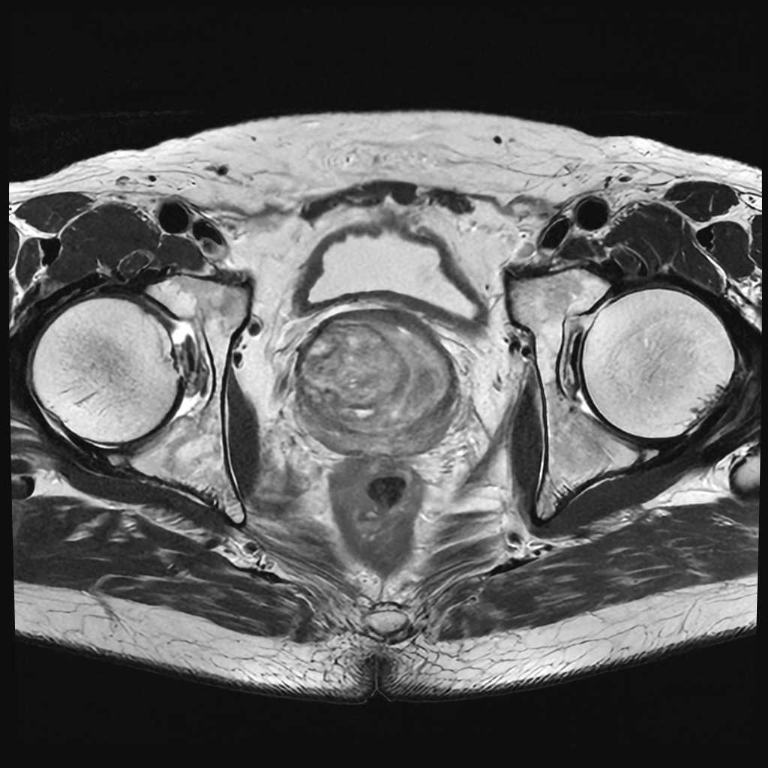

男性器領域

前立腺

前立腺肥大